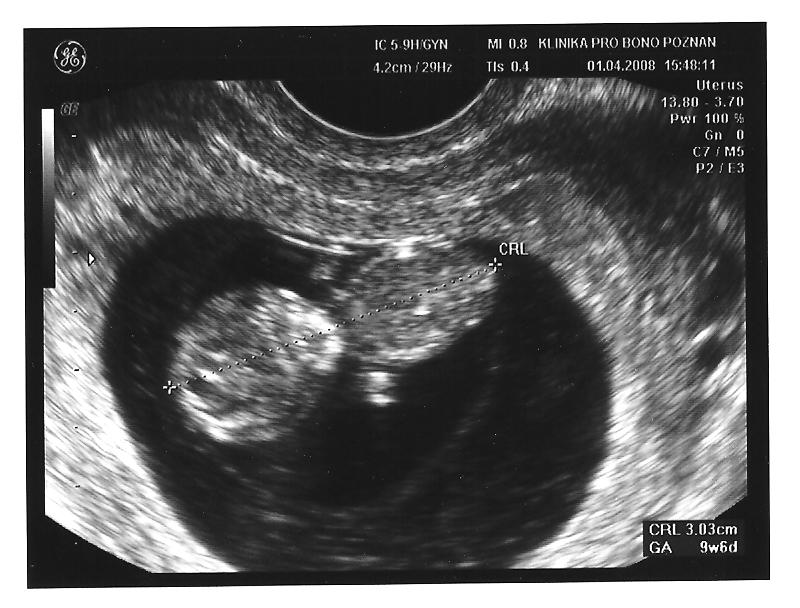

Ja bylam u gina dzidzia ma 3,8 cm wiec urosla serduszko bije i dzidzia sie rusza

a mama czyli ja szczesliwa :-)